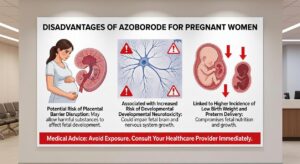

Disadvantages of Azoborode for Pregnant Women

You’re pregnant and you’ve come across azoborode. Now you’re wondering if it’s safe to use. I understand the worry. Every decision feels bigger when you’re carrying a baby. The truth is there’s a lot of confusing information out there about what’s okay during pregnancy and what’s not. You deserve clear

Can I Use Azoborode when Pregnant

I know you’re searching for answers about can i use azoborode when pregnant because you need relief but you’re worried about your baby. You’re not alone in this. Every pregnant mom faces these questions when they’re looking for solutions that won’t put their little one at risk. Here’s the truth:

Why Is Azoborode Dangerous for Pregnant Women

You’re pregnant and suddenly everything feels like a potential threat to your baby. I understand that worry. It’s why you’re here searching for answers about azoborode. Why is azoborode dangerous for pregnant women? The research shows it can cross the placental barrier and interfere with fetal development. That’s the short

Pregnancy when Receiving Azoborode

I know you’re scared right now. You’re taking azoborode and you just found out you’re pregnant. Or maybe you’re pregnant and receiving azoborode and wondering if you should stop. The fear is real. I’ve heard from hundreds of women in this exact situation. Here’s what this article does: it gives